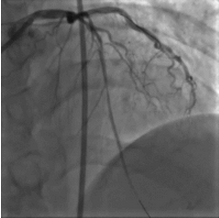

造影结果

2015年10月23日:左主干远段30%狭窄;左前降支近段支架自开口完全闭塞;左回旋支中段长病变,狭窄40%~50%,高位钝缘支粗大,未见狭窄(图1)。右冠粗大、优势型,近段管壁不规则,左室后支、后降支未见狭窄(图2、3)。

图1